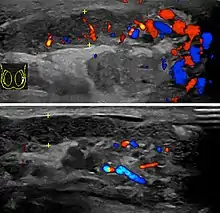

![]() | |

Acute epididymitis with abundant fibrinopurulent exudate in the tubules. | |

Before the advent of sophisticated medical imaging techniques, surgical exploration was the standard of care. Today, Doppler ultrasound is a common test: it can demonstrate areas of blood flow and can distinguish clearly between epididymitis and torsion. However, as torsion and other sources of testicular pain can often be determined by palpation alone, some studies have suggested that the only real benefit of an ultrasound is to assure the person that they do not have testicular cancer.[12]: p.237 Nuclear testicular blood flow testing may be used.[13]